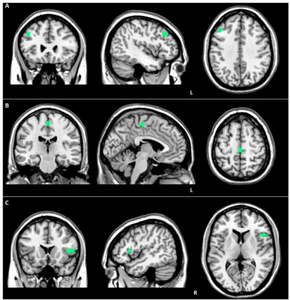

a) Reduced EN connectivity in left middle frontal gyrus (FTD-GRN-) B) Reduced ventral SN connectivity in left medial frontal gyrus (GRN+) c) Reduced dorsal SN connectivity in right precentral gyrus (FTD-GRN+)

Structural MRI scans often reveal frontal lobe and/or anterior temporal lobe atrophy but in early cases the scan may seem normal. Atrophy can be either bilateral or asymmetric.[26] Registration of images at different points of time (e.g., one year apart) can show evidence of atrophy that otherwise (at individual time points) may be reported as normal. Many research groups have begun using techniques such as magnetic resonance spectroscopy, functional imaging and cortical thickness measurements in an attempt to offer an earlier diagnosis to the FTD patient. Fluorine-18-fluorodeoxyglucose positron emission tomography (FDG-PET) scans classically show frontal and/or anterior temporal hypometabolism, which helps differentiate the disease from Alzheimer's disease. The PET scan in Alzheimer's disease classically shows biparietal hypometabolism. Meta-analyses based on imaging methods have shown that frontotemporal dementia mainly affects a frontomedial network discussed in the context of social cognition or 'theory of mind'.[27] This is entirely in keeping with the notion that on the basis of cognitive neuropsychological evidence, the ventromedial prefrontal cortex is a major locus of dysfunction early on in the course of the behavioural variant of frontotemporal degeneration.[28] The language subtypes of frontotemporal lobar degeneration (semantic dementia and progressive nonfluent aphasia) can be regionally dissociated by imaging approaches in vivo.[29]